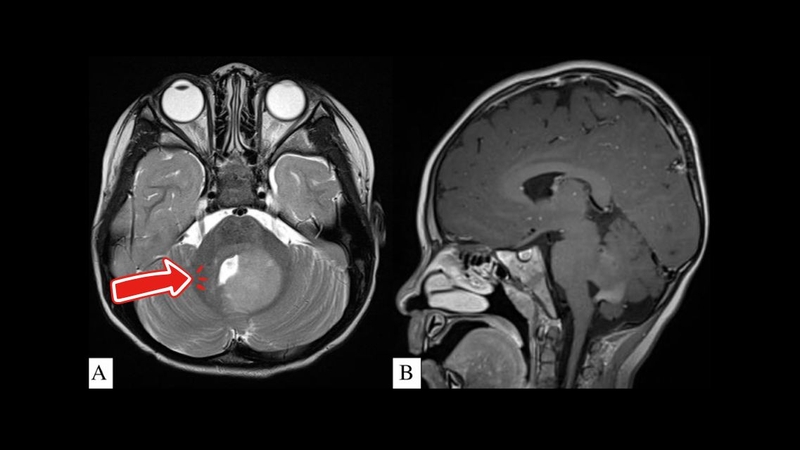

U tiểu não là một dạng u não xảy ra tại vùng tiểu não – cấu trúc quan trọng điều phối vận động và thăng bằng của cơ thể. Dù không phổ biến như các u não ở bán cầu đại não, u tiểu não vẫn tiềm ẩn nhiều nguy cơ nghiêm trọng. Việc nhận biết sớm các triệu chứng và hiểu rõ phương pháp điều trị đóng vai trò then chốt giúp cải thiện tiên lượng căn bệnh này.

U tiểu não là tình trạng khối u phát triển tại vùng tiểu não – một bộ phận nằm ở phía sau thân não, giữ vai trò quan trọng trong việc điều khiển thăng bằng, phối hợp vận động và kiểm soát tư thế.

Các khối u tại đây có thể được phân loại theo bản chất lành hay ác tính. Khoảng 70% các trường hợp u tiểu não ở trẻ em là u lành tính, phổ biến nhất là u tế bào sao thể lông (pilocytic astrocytoma).

Trong khi đó, u nguyên bào tủy (medulloblastoma) là một loại u ác tính thường gặp ở vùng tiểu não của trẻ em. Khoảng 30% các trường hợp u tiểu não là u ác tính, bao gồm cả u nguyên phát như medulloblastoma, ependymoma và glioblastoma, cũng như các trường hợp di căn từ cơ quan khác như phổi, vú, hoặc thận.